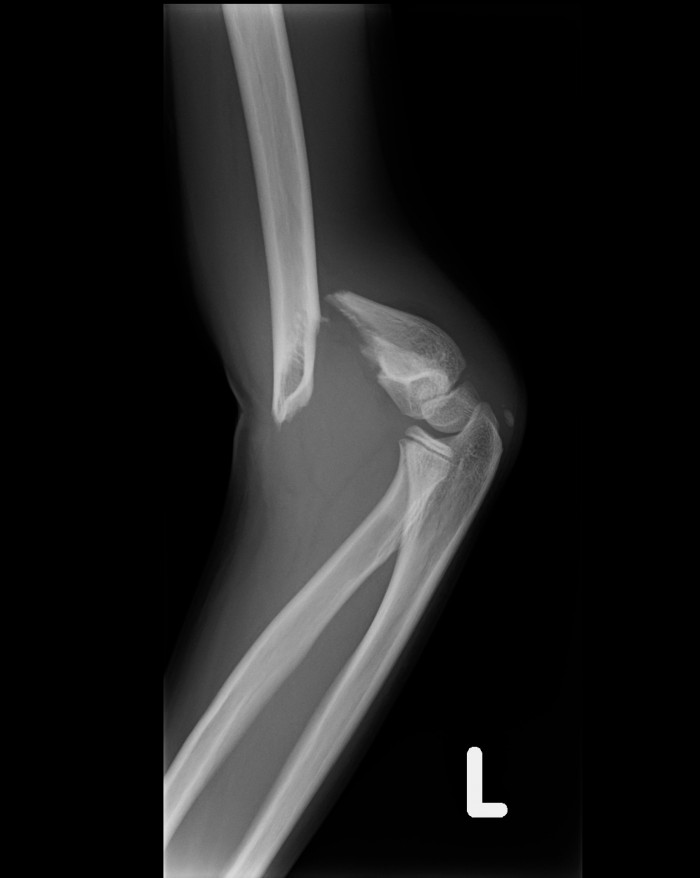

しみずばし鍼灸整骨院では、プロ選手も使用している超音波治療器や最新治療器、鍼灸治療を用いることで、患部の治癒能力を高めます。骨折や脱臼、捻挫、打撲、肉離れなどは包帯を巻くこともあります。重症の場合は、患部の安静を図るために、整形外科で扱っている固定材も使うこともあります。また、レントゲン撮影が必要と判断した場合は、専門医に紹介をしています。